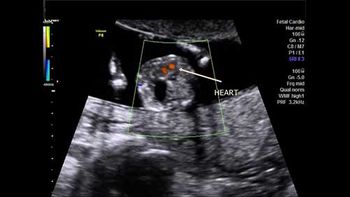

Challenge your diagnostic skills: What's your diagnosis based on these images from a 14-week fetus?